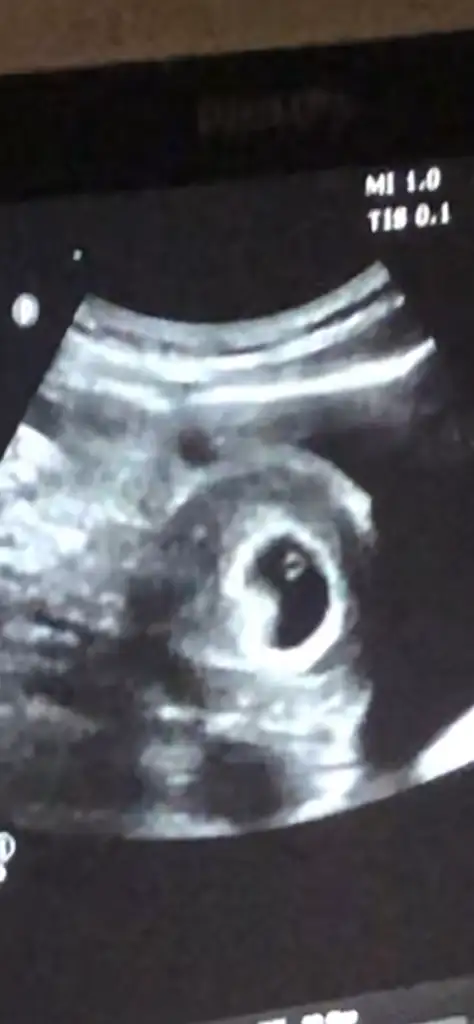

Merhaba bize cinsiyet tahmini yapar mısınız

5., 6., ve 9+5 .haftaya ait karından ultrason görüntüleri :)Eki Görüntüle 3273013 Eki Görüntüle 3273014 Eki Görüntüle 3273015

Rica etsem bana da yorum yapabilir misiniz. 6 haftalık karındanErkek bebek 6 haftalık ultrasona göre kuzum

Başka yok mu canım burda sadece yolk kesesi gözüküyor bebişin konumu belli degilRica etsem bana da yorum yapabilir misiniz. 6 haftalık karından Eki Görüntüle 3273029

Videodan çekmeye çalışmıştım ne olduğunu bilmedenBaşka yok mu canım burda sadece yolk kesesi gözüküyor bebişin konumu belli degil

Buna göre kız canımVideodan çekmeye çalışmıştım ne olduğunu bilmedensanırım çok minik daha